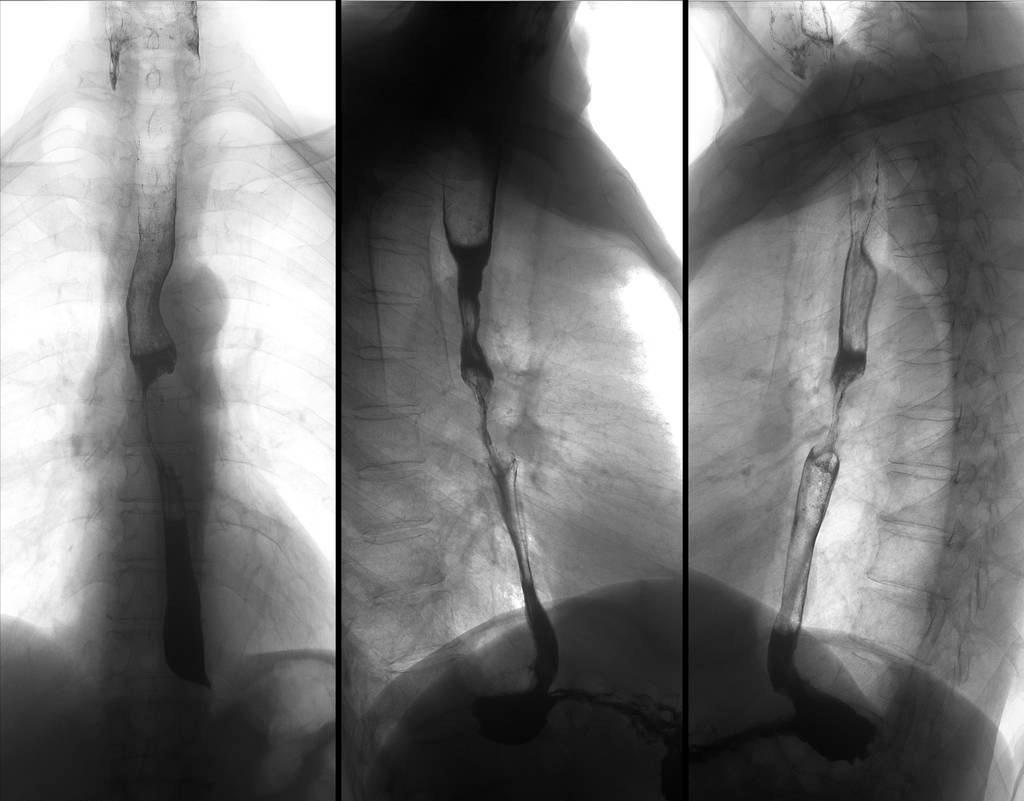

当天下午,结果出来了: II期食管癌,且肿瘤病变已经侵犯到食管肌层。

排除食管癌,做胃镜是性价比最高的,因为胃镜不仅能够诊断胃部问题,还能发现特别细小的早期食管癌,诊断率可以达到80%。